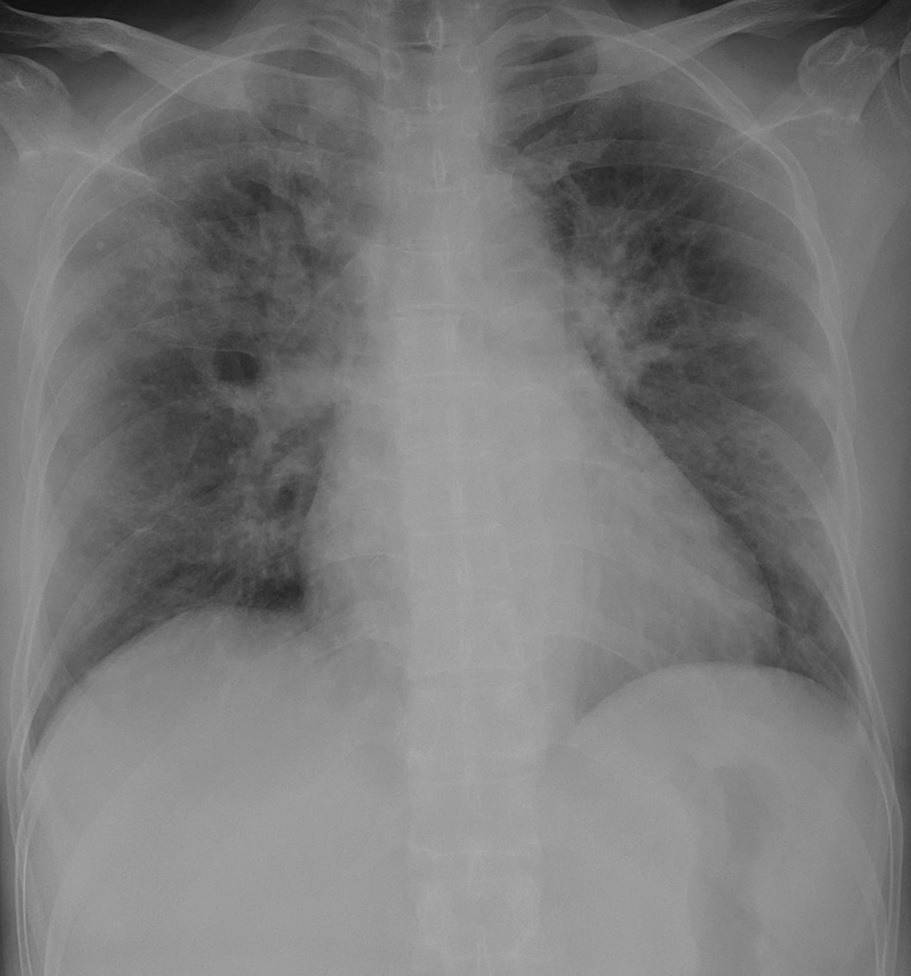

Figure 6 presents image examples for each class retrieved from the RYDLS-20 database. It is worth to mentioning that we have no further information concerning the CXR images with regarding the CXR machine used to take the image, as well as the origin, age and ethnicity of the people whose these images belong to.

Refer to caption

(b) COVID-19.

Figure 6: RYDLS-20 image samples.